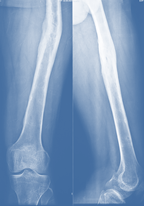

On 14th POD superficial infection was evident. Exploration and surgical toileting was done on same day, wound dressing done daily. Subsequent follow up was going on in improvement of the patient (Figure 2). After 4 months of operation, he was fall down and affected fractured limb (Left lower limb). During physical examination we found moderate tenderness without any abnormal mobility at fractured site. There were no signs of infection. Knee and hip joints movement restricted due to pain. In radiograph there was re-fracture of mid shaft of left femur with plate bending at fracture site with minimal callus but no sequestrum (Figure 3). 200 angulation and 1.5 cm shortening of left lower limb was found. Full Blood Counts (CBCs), ESR and CRP was done. Haemoglobin 13 gm/dl, WBC within normal range but moderate increased of ESR and CRP.

Figure 2 Follow-up x-ray after 3 months.

Figure 3 x-ray after re-fracture due to fall.